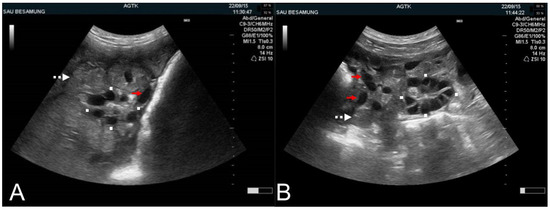

3.2. The Ovary

4.3. Problems with Conception and Farrowing Rate